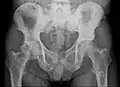

Radio du bassin d'un patient atteint d'un carcinome de la prostate : multiples métastases ostéocondensantes, en particulier sur le sacrum, mais aussi sur l'ilion surtout gauche (à dr. sur l'image), sur la pointe de l'ischion gauche, et sur le fémur proximal gauche. On détecte à l'occasion une arthrose de hanche droite (à g. sur l'image).